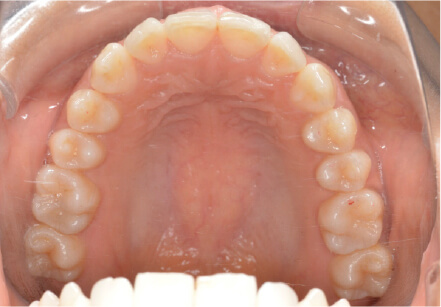

11歳

/

女性

相談内容

上の前歯の歯並びが気になる(マイオスマイルからの移行)

カウンセリング・診断結果

インビザライン、拡大入れながらスペースを作成、下Eは出てきたら削りながら進める

治療内容・方法

全額アライナー矯正 クリアコレクト

術後の経過・現在の様子

クリアライナー使用

治療のリスク

痛み・歯根吸収・歯肉退縮・虫歯・後戻り

費用・治療期間

移行料金220,000円、月々16,500円、1年1ヶ月+myo2年3ヶ月